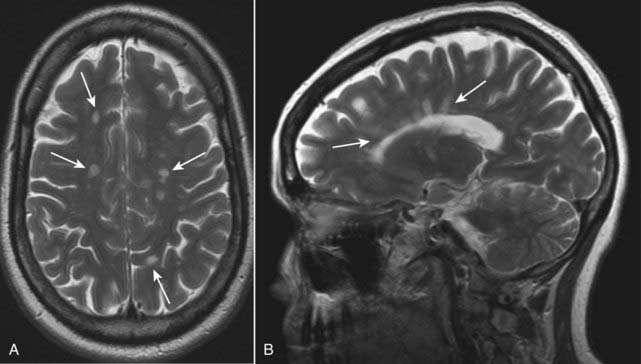

image It characteristically affects myelinated (white matter) tracks with lesions known as plaques. Lesions of multiple sclerosis have a predilection for the periventricular area, corpus callosum, and optic nerves.

imageMRI is the study of choice in imaging multiple sclerosis because of its greater sensitivity than CT in demonstrating plaques both in the brain and spinal cord.

image The lesions produce discrete, globular foci of high signal intensity (white) on T2-weighted images.

image On T1-weighted, nonenhanced images, they are isointense to hypointense, but in acute MS, the lesions enhance with gadolinium on T1-weighted images.

image The lesions tend to be oriented with their long axes perpendicular to the ventricular walls (Fig. 25-31).

image

Figure 25-31 Multiple sclerosis, axial and sagittal MRI.

Lesions of multiple sclerosis have a predilection for the periventricular area, corpus callosum, and optic nerves (solid white arrows). A, The lesions produce discrete, globular foci of high-signal intensity (white) on T2-weighted images. B, Ovoid lesions with their long axis perpendicular to the ventricular surface seen in multiple sclerosis are called Dawson fingers (solid white arrows). MRI is the study of choice in imaging multiple sclerosis because of its greater sensitivity than CT in demonstrating plaques both in the brain and spinal cord.